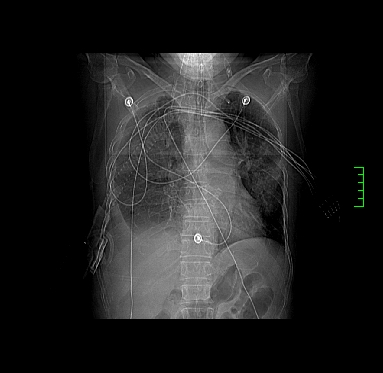

icu病人,几天都没明确诊断。m,76y,咳嗽、咳痰1周,伴气促,右胸痛入院,pe:t38.3c p135 r25 bp135/85。双肺可闻及大量湿罗音,心、腹未见明显异常。诊断:1心衰?2肺部感染?3冠心病?

9号平片